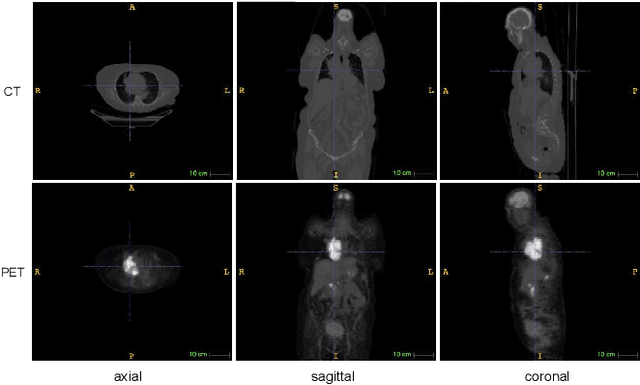

Abstract:Single-modality medical images generally do not contain enough information to reach an accurate and reliable diagnosis. For this reason, physicians generally diagnose diseases based on multimodal medical images such as, e.g., PET/CT. The effective fusion of multimodal information is essential to reach a reliable decision and explain how the decision is made as well. In this paper, we propose a fusion framework for multimodal medical image segmentation based on deep learning and the Dempster-Shafer theory of evidence. In this framework, the reliability of each single modality image when segmenting different objects is taken into account by a contextual discounting operation. The discounted pieces of evidence from each modality are then combined by Dempster's rule to reach a final decision. Experimental results with a PET-CT dataset with lymphomas and a multi-MRI dataset with brain tumors show that our method outperforms the state-of-the-art methods in accuracy and reliability.

Abstract:An automatic evidential segmentation method based on Dempster-Shafer theory and deep learning is proposed to segment lymphomas from three-dimensional Positron Emission Tomography (PET) and Computed Tomography (CT) images. The architecture is composed of a deep feature-extraction module and an evidential layer. The feature extraction module uses an encoder-decoder framework to extract semantic feature vectors from 3D inputs. The evidential layer then uses prototypes in the feature space to compute a belief function at each voxel quantifying the uncertainty about the presence or absence of a lymphoma at this location. Two evidential layers are compared, based on different ways of using distances to prototypes for computing mass functions. The whole model is trained end-to-end by minimizing the Dice loss function. The proposed combination of deep feature extraction and evidential segmentation is shown to outperform the baseline UNet model as well as three other state-of-the-art models on a dataset of 173 patients.

Abstract:Lymphoma detection and segmentation from whole-body Positron Emission Tomography/Computed Tomography (PET/CT) volumes are crucial for surgical indication and radiotherapy. Designing automatic segmentation methods capable of effectively exploiting the information from PET and CT as well as resolving their uncertainty remain a challenge. In this paper, we propose an lymphoma segmentation model using an UNet with an evidential PET/CT fusion layer. Single-modality volumes are trained separately to get initial segmentation maps and an evidential fusion layer is proposed to fuse the two pieces of evidence using Dempster-Shafer theory (DST). Moreover, a multi-task loss function is proposed: in addition to the use of the Dice loss for PET and CT segmentation, a loss function based on the concordance between the two segmentation is added to constrain the final segmentation. We evaluate our proposal on a database of polycentric PET/CT volumes of patients treated for lymphoma, delineated by the experts. Our method get accurate segmentation results with Dice score of 0.726, without any user interaction. Quantitative results show that our method is superior to the state-of-the-art methods.

Abstract:PET and CT are two modalities widely used in medical image analysis. Accurately detecting and segmenting lymphomas from these two imaging modalities are critical tasks for cancer staging and radiotherapy planning. However, this task is still challenging due to the complexity of PET/CT images, and the computation cost to process 3D data. In this paper, a segmentation method based on belief functions is proposed to segment lymphomas in 3D PET/CT images. The architecture is composed of a feature extraction module and an evidential segmentation (ES) module. The ES module outputs not only segmentation results (binary maps indicating the presence or absence of lymphoma in each voxel) but also uncertainty maps quantifying the classification uncertainty. The whole model is optimized by minimizing Dice and uncertainty loss functions to increase segmentation accuracy. The method was evaluated on a database of 173 patients with diffuse large b-cell lymphoma. Quantitative and qualitative results show that our method outperforms the state-of-the-art methods.